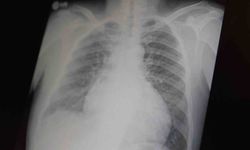

Araklı'da 2020'de dünyaya gelen Ünal'a sağ ventrikül hipoplazisi (kalbin sağ tarafındaki yapıların yeterince gelişmediği, doğumdan itibaren mevcut olan kalp kusuru) teşhisi konuldu.

Yenidoğan döneminde akciğerlere kan akışını sağlamak amacıyla kalbine kateter yöntemiyle stent takılan Miran'a 6 aylıkken de Glenn ameliyatı (bebeğin kalbindeki dolaşım problemini gidermek için yapılan bir operasyon) yapıldı.

Çocuk Kalp Merkezi Koordinatörü ve Çocuk Kardiyolojisi Eğitim Sorumlusu Prof. Dr. Bedri Aldudak, Miran'ın merkeze, kalbinin sağ yapılarının gelişmemesi nedeniyle getirildiğini belirterek, hastaya ilk olarak yaşamsal fonksiyonlarını sürdürebilmesi için kateter yöntemiyle girişim yapıldığını ve kalbine stent yerleştirildiğini söyledi.

Miran'ın tedavi sürecinin aşamalı ilerlediğine işaret eden Aldudak, bu hastalarda kalbin bir tarafının gelişmemesi nedeniyle tam anlamıyla bir anatomik düzelmenin mümkün olmadığını belirtti.

'Bu çocukları yaşatmaya yönelik cerrahi müdahaleler uyguluyoruz. Genellikle 2 ya da 3 ameliyat gerekiyor. Hastamıza ilk müdahaleyi stentle gerçekleştirdik. Bu işlemler tek seferde yapılamaz, çocuğun gelişmesi gerekir. Genellikle doğumdan sonra 6 ay civarında ve 3-5 yaş arasında olmak üzere aşamalı olarak bu ameliyatları gerçekleştiriyoruz.'